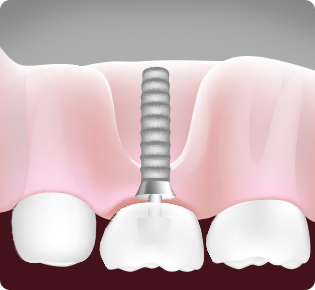

인공치아 뿌리 식립

이렇게 잇몸뼈 이식술을 통해 인공치아 기둥뿌리를 확실히

심어주는 것입니다!

04임플란트 식립(2차수술)

뼈 이식재가 잇몸뼈로 전환된 걸 확인 후 임플란트를 이상적인 위치에 식립합니다.

05보철물장착

2차 수술 후 잇몸이 아문 다음 환자의 상태를 살펴본 후 보철물을 장착합니다.